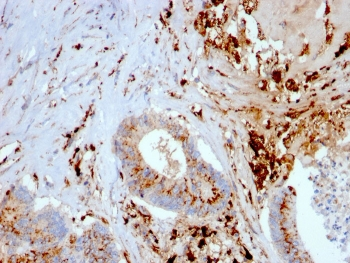

Cathepsin D Antibody

| Description | Cathepsin D Antibody |

| Tested applications | FC, ICC, IHC, IP, WB |

| Reactivity | Human, Mouse |